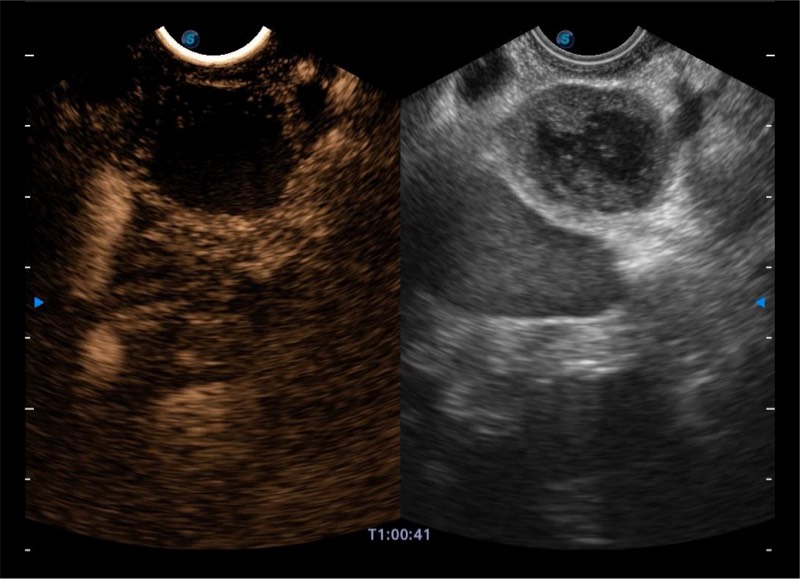

搭载百万级CMOS成像技术

及自主研发凸阵换能器,

可呈现优质的内镜和超声画面

基于二十年的超声技术积累,开立提供了最新一代的独立超声主机,在提供高质量图像的同时满足多学科使用。具备常见多普勒技术并提供弹性成像、声学造影等高端影像技术。新一代传感器具有更强的抗干扰能力并减少图像伪影。

150°超声扫描角度

4-12MHZ宽频输出